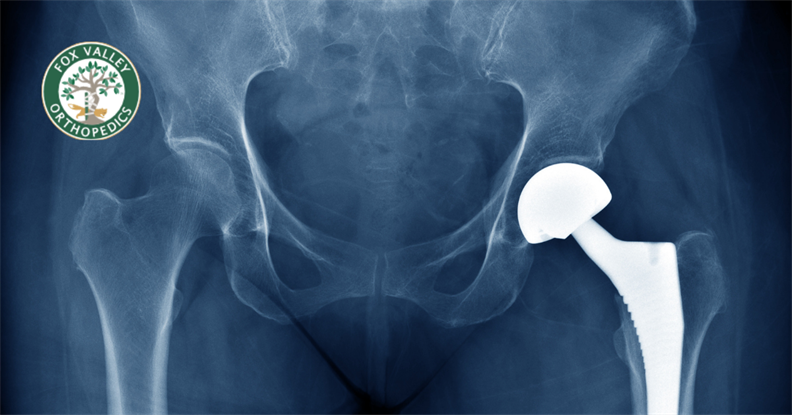

Ensuring a Successful Joint Replacement Although many people push through minor aches and pains everyday, chronic joint ...